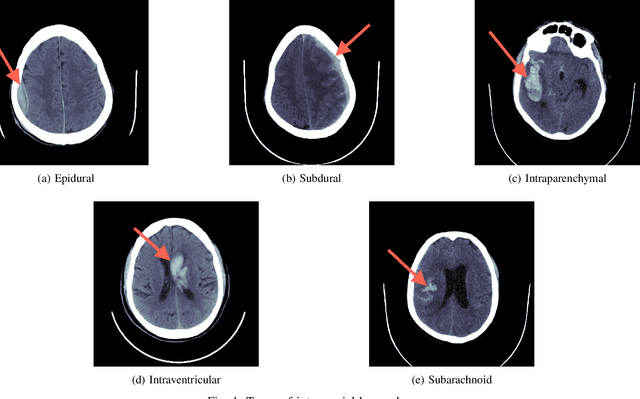

Abstract:Intracranial hemorrhage occurs when blood vessels rupture or leak within the brain tissue or elsewhere inside the skull. It can be caused by physical trauma or by various medical conditions and in many cases leads to death. The treatment must be started as soon as possible, and therefore the hemorrhage should be diagnosed accurately and quickly. The diagnosis is usually performed by a radiologist who analyses a Computed Tomography (CT) scan containing a large number of cross-sectional images throughout the brain. Analysing each image manually can be very time-consuming, but automated techniques can help speed up the process. While much of the recent research has focused on solving this problem by using supervised machine learning algorithms, publicly-available training data remains scarce due to privacy concerns. This problem can be alleviated by unsupervised algorithms. In this paper, we propose a fully-unsupervised algorithm which is based on the mixture models. Our algorithm utilizes the fact that the properties of hemorrhage and healthy tissues follow different distributions, and therefore an appropriate formulation of these distributions allows us to separate them through an Expectation-Maximization process. In addition, our algorithm is able to adaptively determine the number of clusters such that all the hemorrhage regions can be found without including noisy voxels. We demonstrate the results of our algorithm on publicly-available datasets that contain all different hemorrhage types in various sizes and intensities, and our results are compared to earlier unsupervised and supervised algorithms. The results show that our algorithm can outperform the other algorithms with most hemorrhage types.